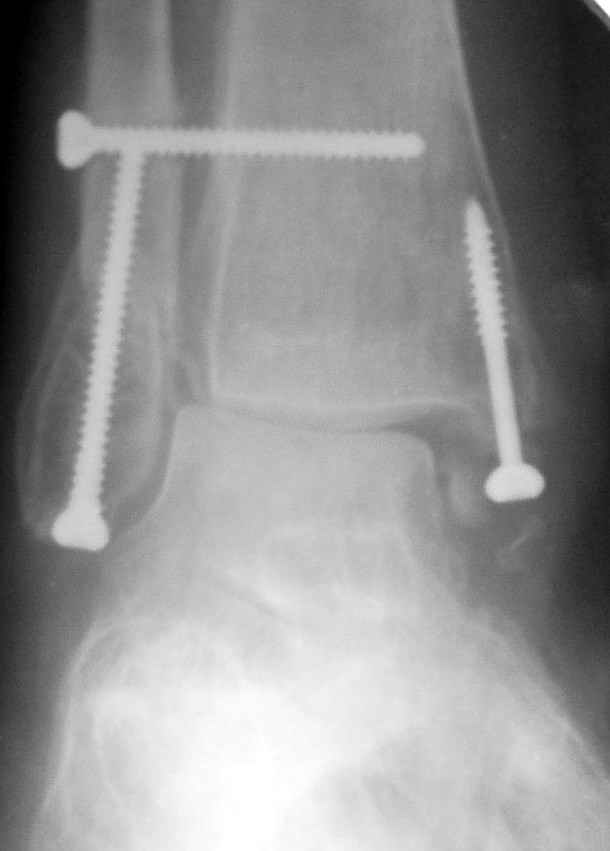

Ниже рентгенограммы

12 января прямой

|

12 января боковой

12 января трехчетвертной